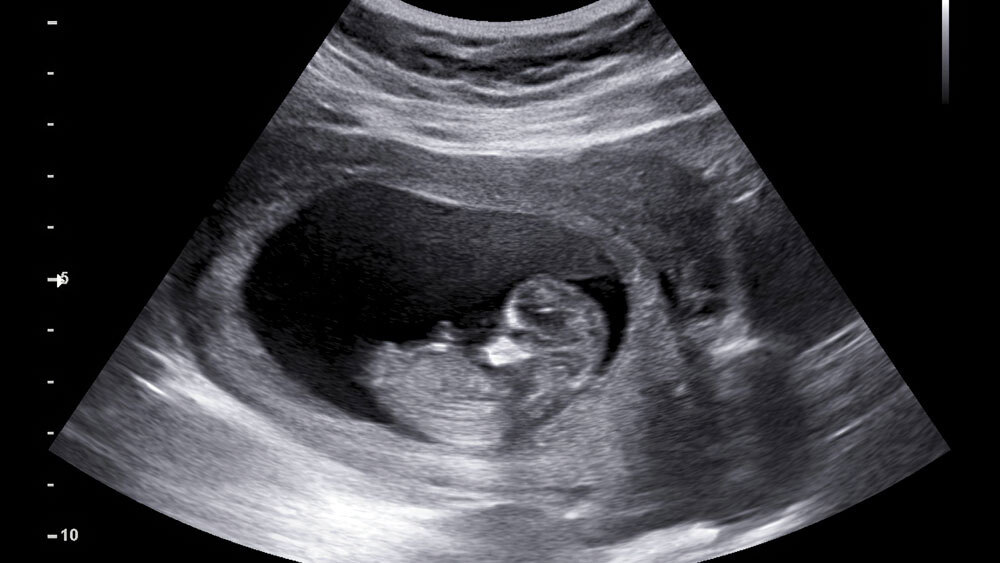

Обнаружен «выключатель», запускающий развитие органов в эмбрионе

На ранних стадиях развития млекопитающих кластеры эмбриональных клеток определяют формирование жизненно важных органов — сердца, легких, печени и других. Это крайне важный процесс в исследованиях наук о жизни, и его лучшее понимание поможет в решении проблем врожденных заболеваний, таких как пороки сердца, и продвижении регенеративной медицины.

Чтобы раскрыть причины аномалий развития органов, команда под руководством профессора Юго-Восточного университета Линь Чэнци провела одноклеточный пространственный омиксный анализ эмбрионов мышей, отслеживая динамический процесс формирования органов.

Их работа выявила зону определения зачатков — критическую область, в которой во время эмбрионального развития появляются первые примитивные структуры развивающихся органов.